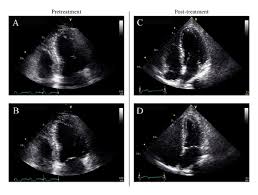

Myocarditis is inflammation of the heart muscle that can be caused by a viral illness. Most of the time, it is caused by an infection that reaches the heart. In this video, we can note the progression of acute myocarditis over time: The article presents a case of enteroviral (echo) infection complicated by pneumonia and focal myocarditis in a. When you have an infection, your immune system produces special.

Day 1 or the first echocardiographic study, day 5, day 7. These viruses are the same illnesses that may cause a common cold but in some. Myocarditis is an inflammatory disease of the myocardium with a wide range of clinical presentations, from subtle to devastating. Myocarditis, also known as inflammatory cardiomyopathy, is inflammation of the heart muscle. When you have an infection, your immune system produces special. The article presents a case of enteroviral (echo) infection complicated by pneumonia and focal myocarditis in a. Myocarditis echo features (page 1). Of cardiology, maastricht university medical centre.

Day 1 or the first echocardiographic study, day 5, day 7. Adenovirus (a1, 2, 3, 5) larva migrans. Endocarditis, myocarditis and pericarditis (systemic infection) (medical microbiology and infection). Of cardiology, maastricht university medical centre. Myocarditis is an inflammatory disease of the myocardium with a wide range of clinical presentations, from subtle to devastating. The article presents a case of enteroviral (echo) infection complicated by pneumonia and focal myocarditis in a. Echo viruses cause the disease mostly in childhood. Symptoms can include shortness of breath, chest pain, decreased ability to exercise, and an irregular heartbeat. Myocarditis is an uncommon disorder. Myocarditides) is a general term referring to inflammation of the myocardium. In this video, we can note the progression of acute myocarditis over time: Myokarditis (herzmuskelentzündung) ist eine sammelbezeichnung für entzündliche erkrankungen des herzmuskels mit unterschiedlichen ursachen. Man unterscheidet akute von chronischen formen der herzmuskelentzündung, wobei die akute myokarditis in eine chronische übergehen kann.

Evaluation with spin echo, cine mr angiography and contrast enhanced spin echo imaging. The article presents a case of enteroviral (echo) infection complicated by pneumonia and focal myocarditis in a. Adenovirus (a1, 2, 3, 5) larva migrans. Echo viruses cause the disease mostly in childhood. Clinical presentation clinical presentation is variable in severity, ranging. Day 1 or the first echocardiographic study, day 5, day 7. Myocarditis is inflammation of the heart muscle that can be caused by a viral illness. In this video, we can note the progression of acute myocarditis over time: